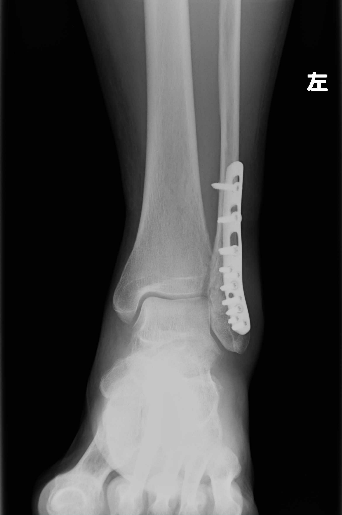

手術療法

骨の転位が強く、骨癒合乏しい場合は手術療法を選択します。

手術方法は①プレート固定、②ピンニング固定、③スクリュー固定